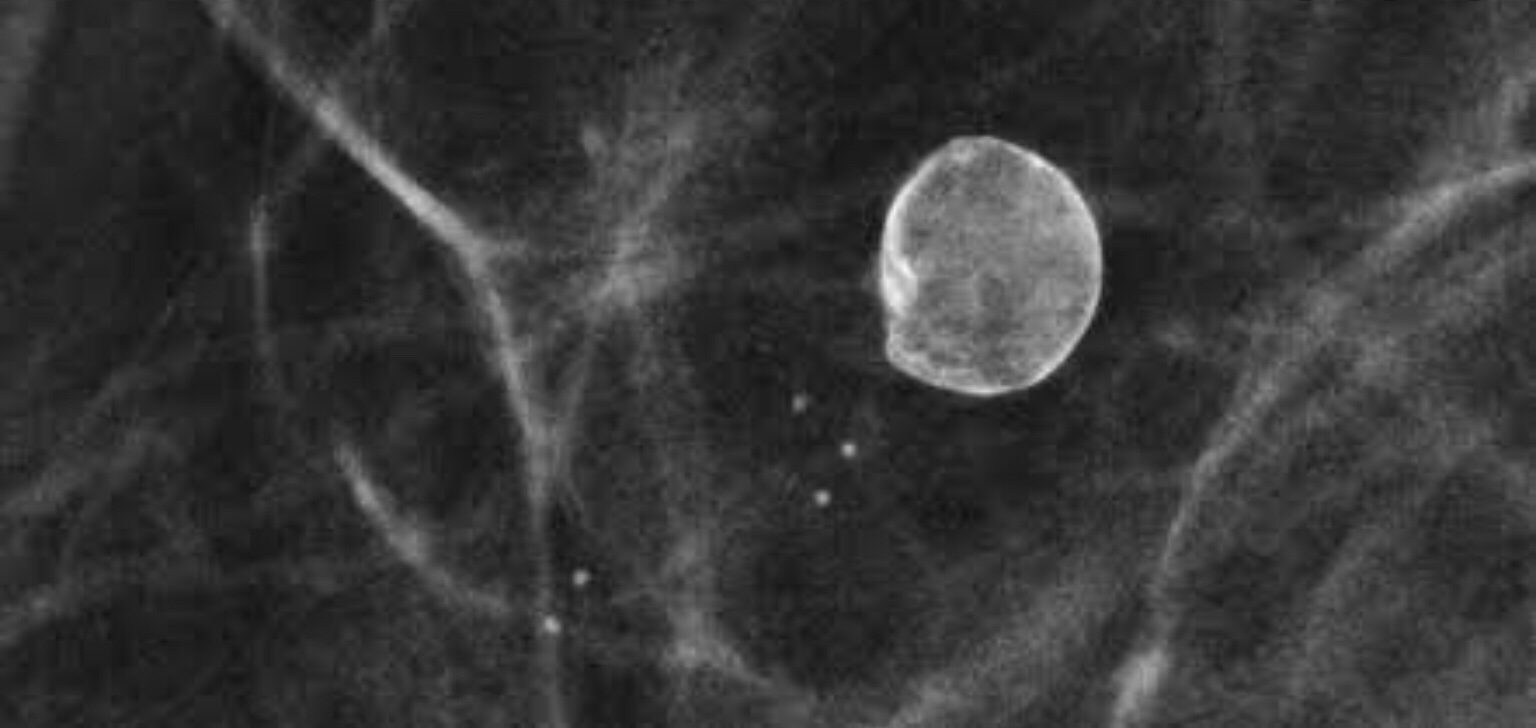

Simple Breast cyst: cysts are fluid containing cavities and are very well seen on the Ultrasound of the breast. But this is how they would appear on a mammogram. This thin walled cyst is accompanied by small smooth round to oval calcifications suggesting a benign lump.